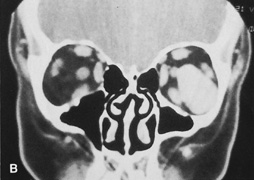

Fig. 16. A. Patient with right orbital cellulitis. B. Coronal CT scan demonstrating subperiosteal abscess formation from frontal and ethmoidal sinusitis. C. Frontoethmoidal orbitotomy incision marked for abscess drainage.

The periosteum is exposed and incised with a Freer elevator and then is reflected off the bone posteriorly. It is generally quite adherent to the curved contour of the medial canthal bones, especially at the medial canthal tendon. The anterior lacrimal crest is encountered inferiorly. Care should be taken not to damage the lacrimal sac with the elevator. The posterior lacrimal crest is visible behind the sac. Adequate mobilization of the periosteal connections to the anterior lacrimal crest gives a large area of exposure. The periosteal elevation is carried superiorly in the area of the trochlea. Elevation of the periosteum opens the subperiosteal space. Blood or pus caused by fracture or infection, if present in this space, is encountered at this point.

Indications

The frontoethmoidal medial orbitotomy allows access for a variety of procedures in the subperiosteal and peripheral surgical spaces and sinuses (Fig. 17). Its main use is for processes involving both the frontal or ethmoid sinuses and the orbit. Entrance into the subperiosteal space is obtained easily. Drainage of subperiosteal blood or pus occurs as the space is entered.

Fig. 17. Schematic demonstration of areas amenable to frontoethmoidal orbitotomy. Coronal (A) and axial (B) views. This approach can be used for exposure of the medial orbit, ethmoid and sphenoid sinuses, and optic canal.